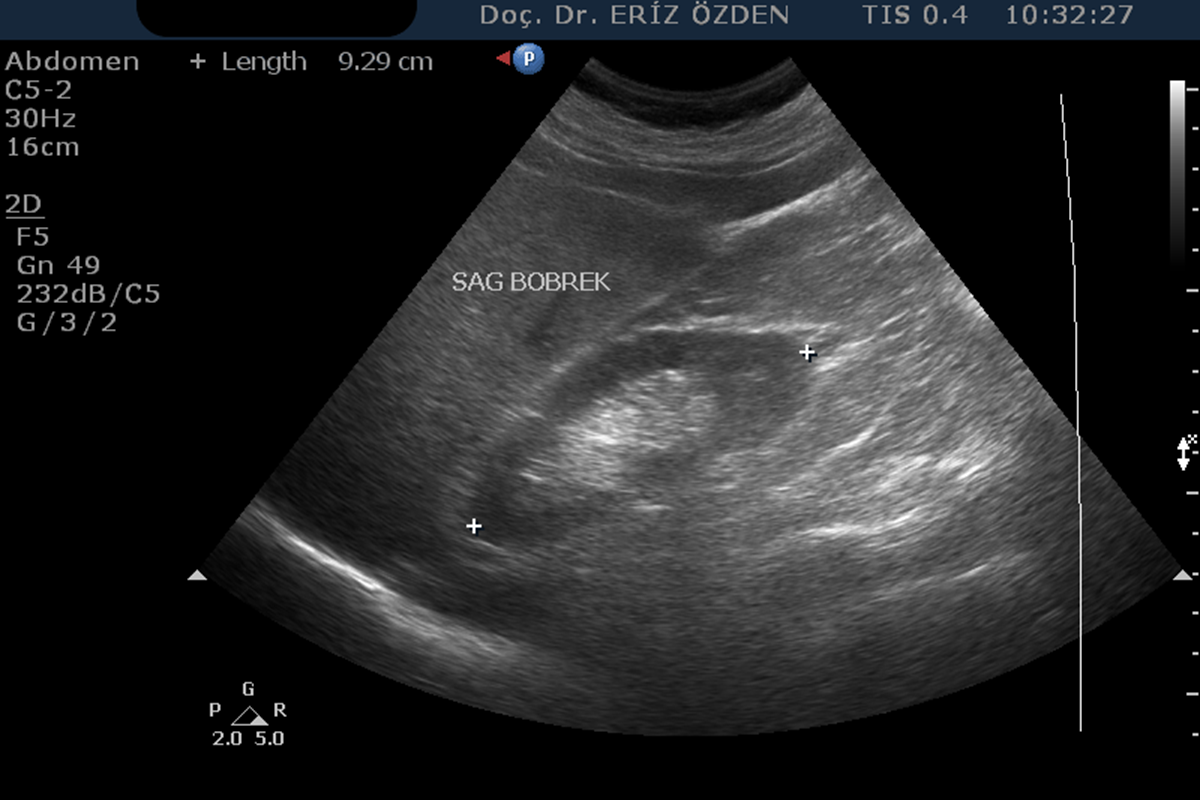

Böbreklerin incelendiği Ultrason tetkikidir. Böbreklerin boyutları, kalınlıkları, yapıları incelenir. Böbreklerin içindeki idrar toplayan keseciklerin (toplayıcı sistem) çaplarına, bunlarda genişleme (hidronefroz) olup olmadığında bakılır. Ayrıca böbrek taşları, böbrek kistleri ve böbrek tümörleri açısından ayrıntılı inceleme yapılır. Yaklaşık 20 dakika süren bir tetkik olup, herhangi bir ön hazırlığı yoktur.